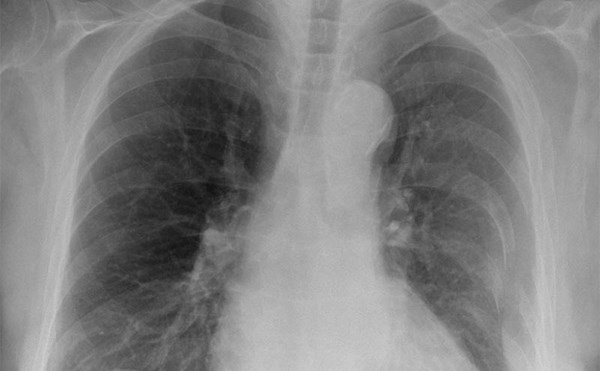

COPD Exacerbation

This is a 55 year old female with a history of CHF and COPD who presents with cough and shortness of breath for 3 days.

A Case of Severe COPD

63 yo smoker with extensive copd on home oxygen comes to the emergency department short of breath.